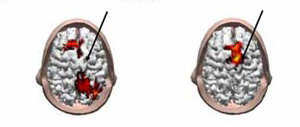

Ученые сравнили отклик нервных клеток на стимулирующие электромагнитные импульсы, получаемые в состоянии бодрствования и глубокого сна. В первом случае, пишет PhysOrg, электромагнитное воздействие, приложенное к произвольно выбранной области мозга, сопровождалось постепенно затухающими волнами возбуждения, разбегающимися в разных направлениях по всему мозгу. Во втором сигнал затухал быстро, не покидая пределов функционально изолированных областей.